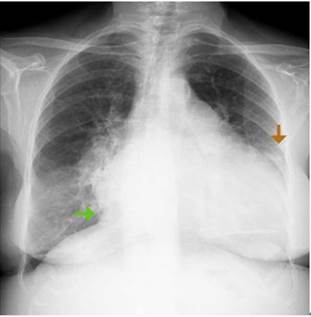

Lab tests results yielded blood arterial gases without oxygenation disorder, compensated respiratory alkalosis, lactate: 2.5 mmol/L, blood count with mild heterogeneous normocytic hypochromic anemia, hemoglobin: 11.2 g/dL, mean corpuscular volume: 81 fL, mean corpuscular hemoglobin: 25.5 pg, red cell distribution width: 17.7% and platelets, leukocytes, sodium, and potassium within normal ranges. Chest x-ray showed an increased cardiothoracic ratio and angiosclerotic changes with calcified plaques and signs of precapillary pulmonary hypertension. Furthermore, mixed involvement of the parenchyma was found with a greater predominance of parahilar alveolar and lower lobe involvement, with a moderate amount of bilateral free fluid predominantly in the left hemithorax (Figure 3).

Source: Document obtained during the course of the study.

Figure 3 Chest x-ray. Green arrow: overall cardiomegaly with cardiothoracic ratio of 0.7; Orange arrow: left pleural effusion.